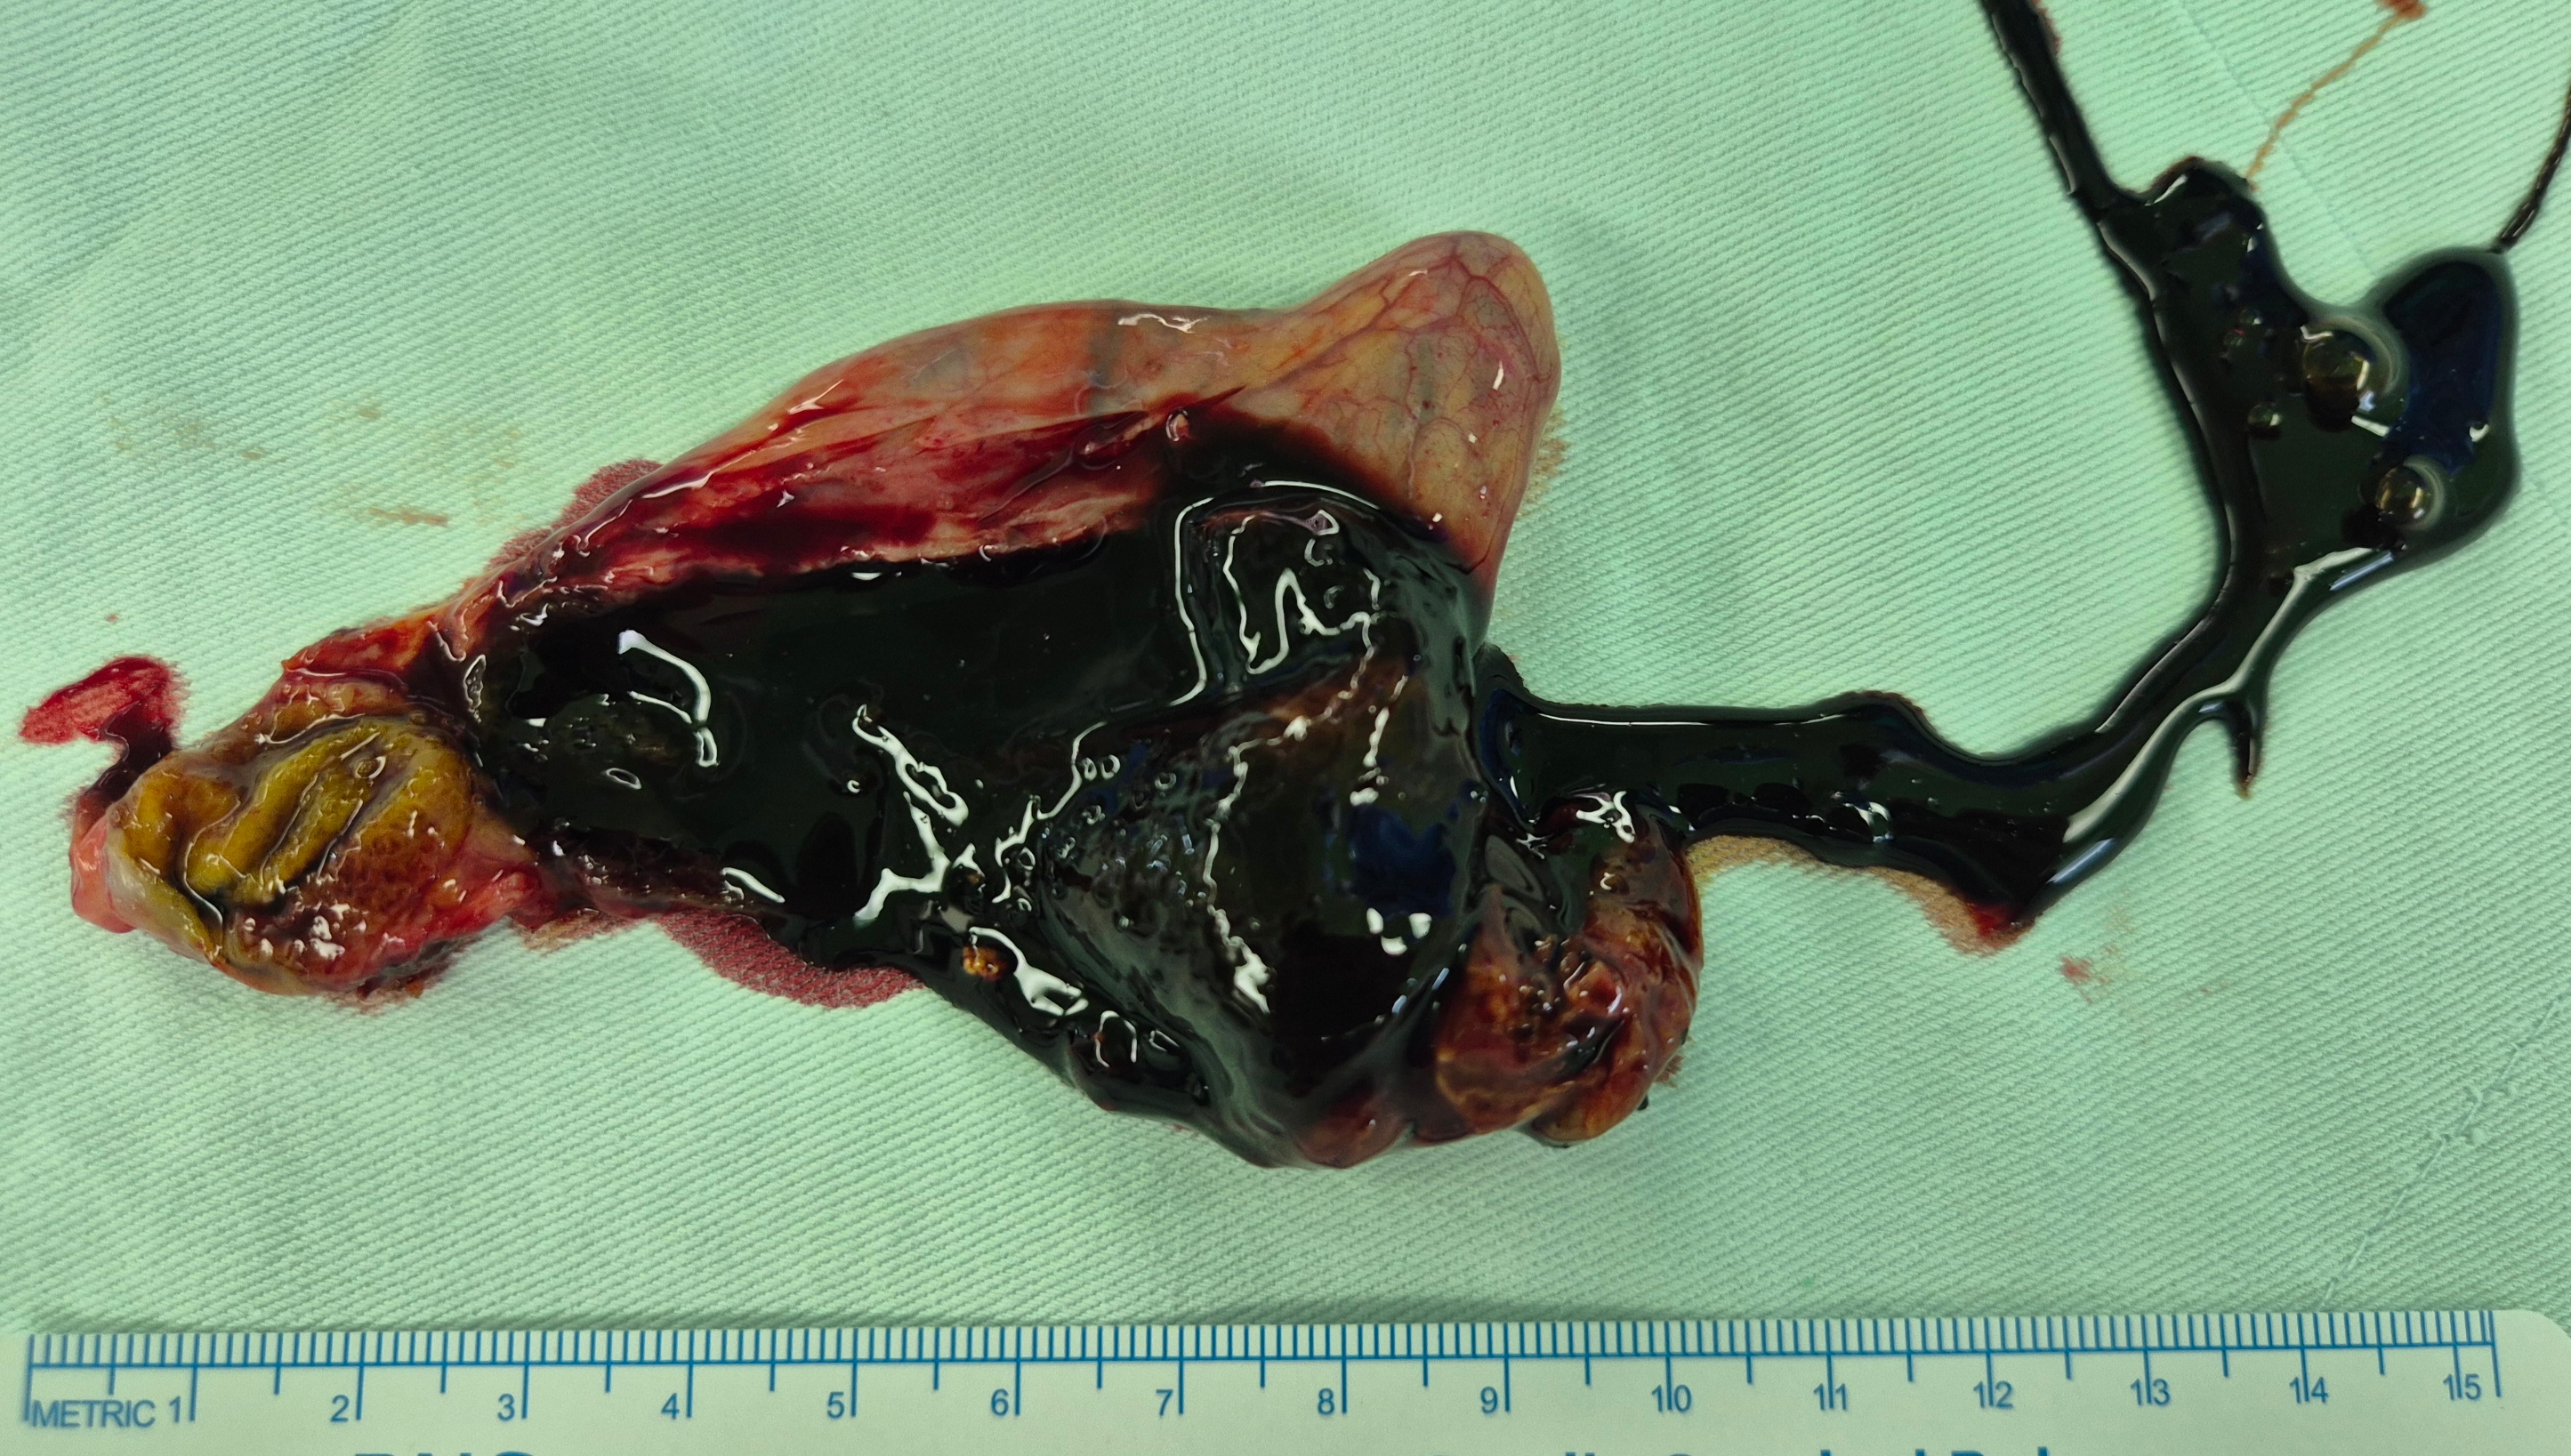

상복부 불편감으로 시행한 복부 ct상 만성 담석 담낭염으로 확인되어,

방금 단일공 복강경 담낭절제술을 시행했습니다.

수술은 20분 걸렸습니다.